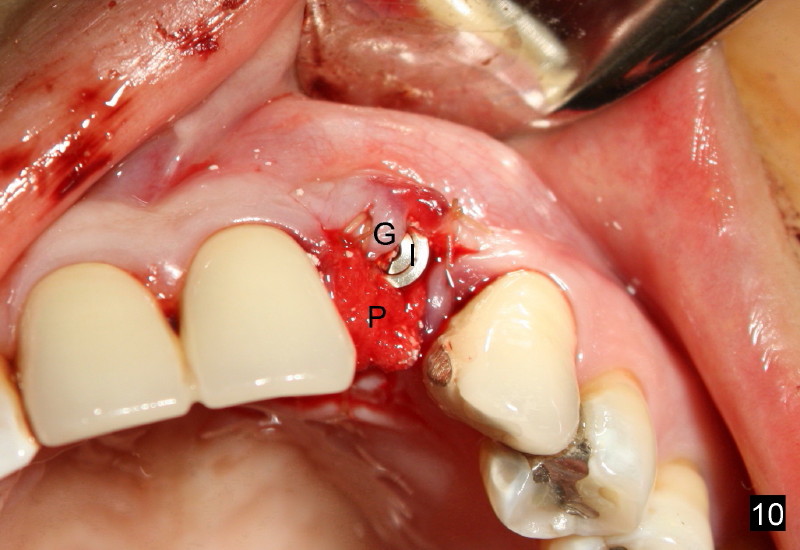

Segmental Osteotomy for Misplaced Implant

This corrective surgery was performed by Dr. Bernee Dunson.

Xin Wei, DDS, PhD, MS 1st edition 12/21/2011, last revision 12/23/2011